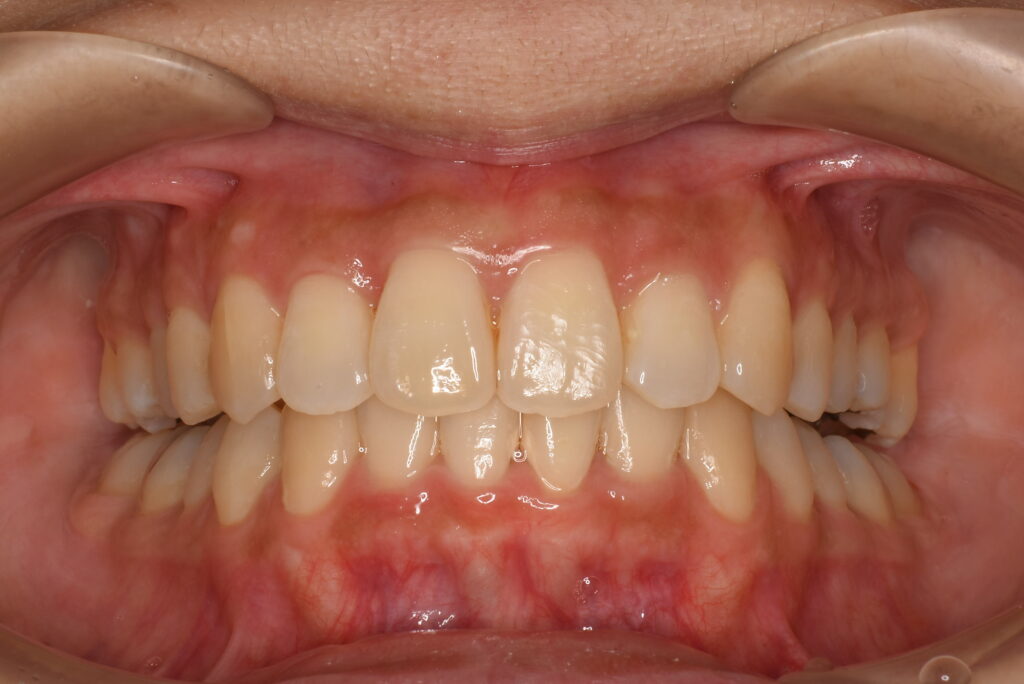

- AFTER

| 治療内容 | 患者様は、上顎前歯の突出や歯列の叢生(ガタつき)、笑った際に歯ぐきが見えすぎること(ガミースマイル)を主訴に来院されました。 診査の結果、抜歯を行うと歯軸の傾斜や歯列の陥没が懸念されたため、非抜歯でのインビザライン治療を計画しました。 |